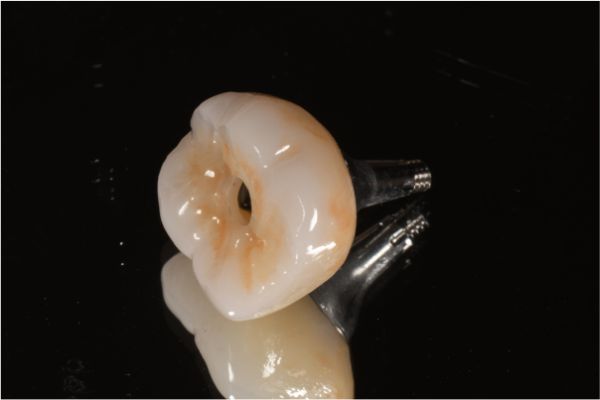

螺絲固位全鋯冠